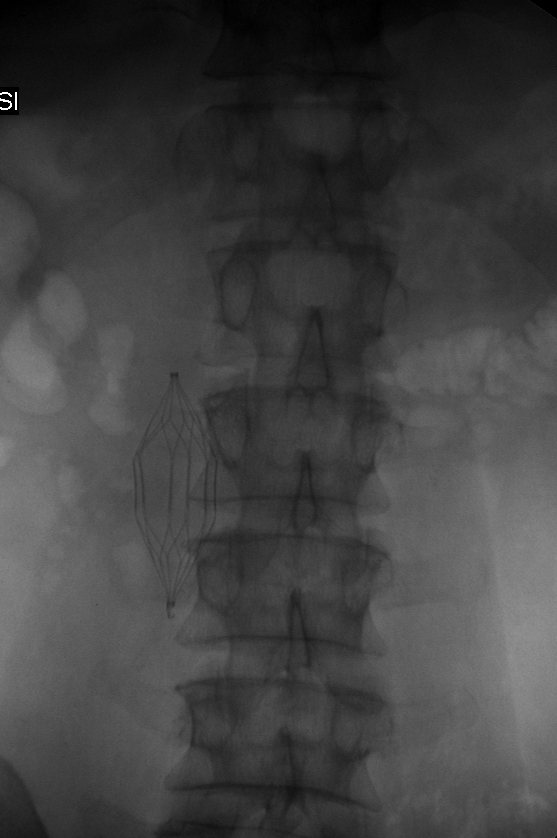

Frontal abdominal radiograph before filter retrieval.

Published July 26, 2014 at 557 × 838 in Case 4: Retrieving IVC filters. Ken U. Ekechukwu, MD, MPH, FACP. .